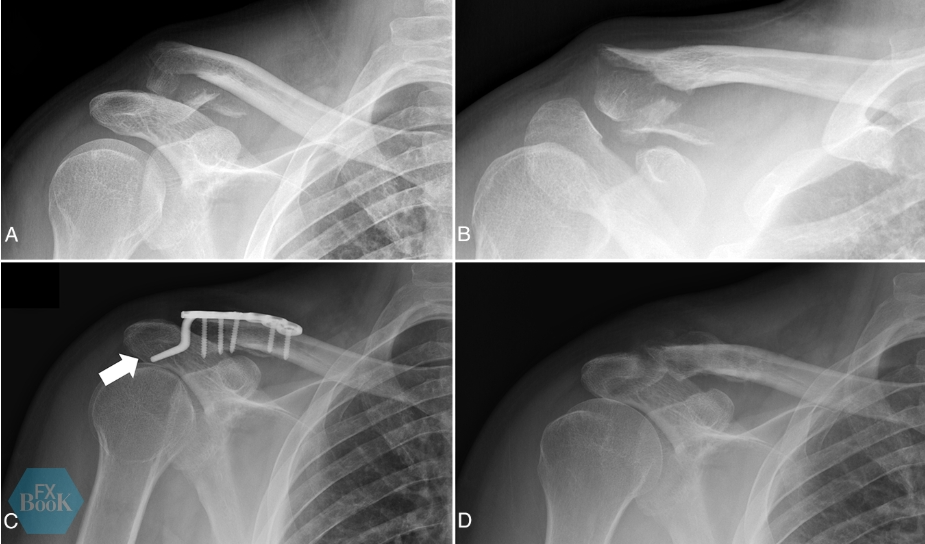

图2,(A、B)一位48岁男性因跌倒导致的锁骨远端骨折(Neer V型)平片。患者存在明显临床畸形并要求手术治疗。(C)钩钢板固定术后6周X线片。在附着喙锁韧带的锁骨下方骨块置入2号高强缝线,骨折固定后跨越钩钢板打结。选择钩钢板是由于远端骨块严重粉碎。此外患者有癫痫病史(虽控制良好),但考虑到术后癫痫发作可能影响固定稳定性。使用钩钢板时需注意:钩部形态需与肩峰下表面弧度匹配(白箭),避免过度复位。(D)术后9个月取出钩钢板后的X线片显示远端锁骨已达解剖对齐的骨性愈合。

图3,(A)一名58岁男性因跌倒导致移位性远端锁骨骨折(Neer II型)平片。患者存在明显畸形,要求手术治疗。(B)初次术后X线片显示采用单纯锁定钢板固定(未行喙锁韧带加强)。(C)3个月随访X线片显示远端锁骨骨折已愈合,但出现肩锁关节失效(可见喙锁距离增大及远端锁骨相对于肩峰上移)。